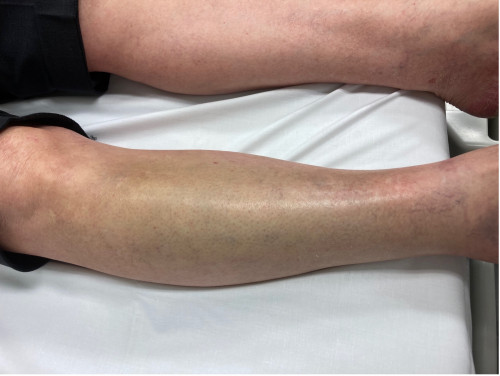

Bei Betrachtung der Unterschenkel zeigt sich folgender klinischer Befund: